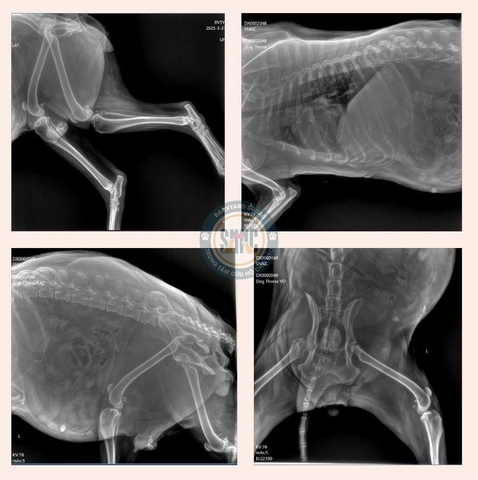

Sau khi được thăm khám, bác sĩ kết luận: bé bị tổn thương thần kinh nặng dẫn tới liệt hai chi sau, vú có hạch, tổn thương cơ nặng, rách da vùng bụng với nguy cơ nhiễm trùng cao, tổn thương nội tạng. Phần cơ thành bụng trái bị tổn thương và bầm tím nặng, thể trạng bé yếu, đau nhiều... tỷ lệ tử vong khoảng 60 - 70%.